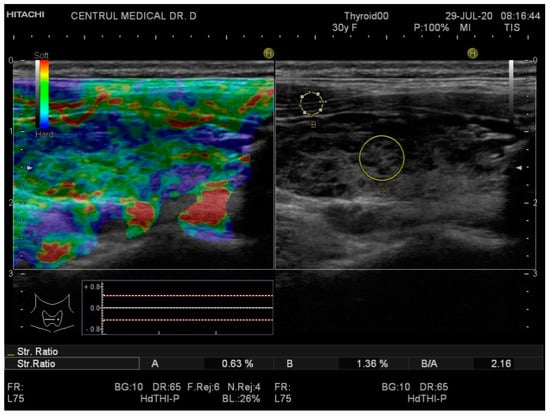

Real-time elastography was performed after conventional US during the same visit. The stiffness measurements were collected in the same session as the grey-scale US evaluation. The probe was placed perpendicularly to the skin and repetitive, light compression was applied avoiding lateral movement. All images were obtained in the longitudinal plane. A blue-green-red color map was displayed with blue indicating no strain (high stiffness), green indicating intermediate stiffness and red representing soft tissue. In order to calculate the strain ratio (SR), two regions of interest (ROI) were placed consequently. The first one, ROI A, was the thyroid tissue while the second one, ROI B, was the sternocleidomastoid muscle in front of the ipsilateral thyroid parenchyma. Figure 1 and Figure 2 below illustrate the SE image and calculation of the SR in normal thyroid tissue and, respectively, in a patient with CAT. Five consecutive measurements were made for each lobe and the mean value was considered in the final evaluation. The SR was calculated and displayed automatically for each lobe.

Figure 2. Strain elastography (left) and conventional US (right) of a patient diagnosed with chronic autoimmune thyroiditis (CAT)—right thyroid lobe. The yellow circle A is the local ROI on the thyroid tissue; the yellow circle B is the local ROI on the adjacent sternocleidomastoid muscle. SR = 2.16.